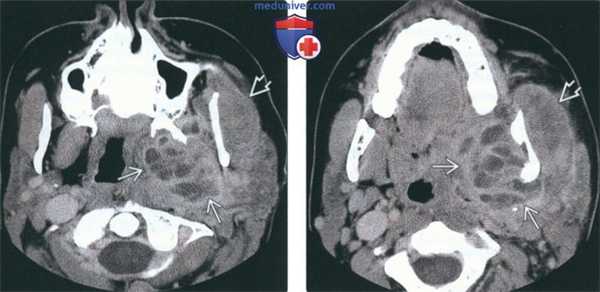

(Слева) На аксиальной КТ с КУ определяется большой многокамерный абсцесс внутреннего ЖП с вовлечением крыловидных мышц. Обратите внимание на утолщение и отек жевательной мышцы в наружном жевательном пространстве. У этого пациента 21 года девять месяцев назад был удален моляр слева, после чего появилась оталгия в сочетании с тризмом, неверно расцененные как проявления синдрома ВНЧС.

(Справа) На аксиальной КТ с КУ у этого же пациента определяется дальнейшее распространение абсцесса внутреннего ЖП в и отек жевательной мышцы.

(Слева) При КТ с КУ в аксиальной проекции определяется гигантский многокамерный абсцесс медиальных отделов жевательного пространства, распространяющийся на крыловидные мышцы. Обратите внимание на отек и припухлость жевательной мышцы в латеральном жевательном пространстве. Пациентка - девушка 21 года, которой девять месяцев назад был удален левый нижний моляр. Все это время она предъявляла жалобы на тризм и боль в ухе, которые врачи ошибочно принимали за заболевание височно-нижнечелюстного сустава.

(Справа) При КТ с КУ в аксиальной проекции у этой же пациентки видно, что абсцесс распространяется в нижележащие ткани. Также имеется отек жевательной мышцы.